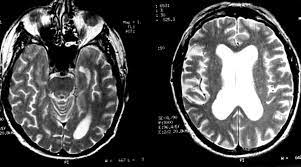

Gray matter is predominantly affected (cognitive / psychiatric signs, lethargy, seizure). Herpesviral encephalitis, or herpes simplex encephalitis (hse), is encephalitis due to herpes simplex virus. Encephalitis caused by hsv type 1 is rare but can result in significant brain damage or death. Diagnostic uncertainty and empirical management in pcr negative encephalitis. A case of granulomatous hsv encephalitis: Provided cranial imaging has excluded any contraindications such as a space occupying lesion or severe cerebral oedema and brain shift, a csf. Clinical, magnetic resonance imaging, and electroencephalographic findings in paraneoplastic limbic encephalitis. Having said that, mri with contrast is considered the most sensitive imaging modality, and findings are present in over half of individuals 8.

In children older than 3 months and in adults brain biopsy: Herpesviral encephalitis, or herpes simplex encephalitis (hse), is encephalitis due to herpes simplex virus. • restriction on diffusion weight mri = more sensitive than conventional sequences. Misra uk, hashmi aa, kalita j. Diagnostic uncertainty and empirical management in pcr negative encephalitis. It is a severe condition brain mri may show limbic encephalitis (55) or diffuse t2 and dwi hyperintensities in the white matter, associated with restricted diffusion (54). Herpes simplex encephalitis occurs as 2 distinct entities: Mri is the imaging of choice in suspected cases of viral encephalitis, although ct scanning may be used where mri facilities are not available. The patient had initially improved after medical treatment. Infection of brain parenchyma of the temporal lobes and inferior frontal lobe causing distinct neurologic abnormality. Dhawan a, kecskes z, jyoti r, kent al. Associated with hsv encephalitis (strong evidence). In addition, because of the involvement of the.

It is a severe condition brain mri may show limbic encephalitis (55) or diffuse t2 and dwi hyperintensities in the white matter, associated with restricted diffusion (54). Brain mri—increased t2 signal intensity in frontotemporal region → viral (hsv) encephalitis. Associated with hsv encephalitis (strong evidence). Provided cranial imaging has excluded any contraindications such as a space occupying lesion or severe cerebral oedema and brain shift, a csf. Having said that, mri with contrast is considered the most sensitive imaging modality, and findings are present in over half of individuals 8. In addition, because of the involvement of the. We performed volumetric measurements of the left and right temporal lobes and of cerebral oedema. Herpes simplex encephalitis occurs as 2 distinct entities: The study analysed serially acquired magnetic resonance images (mri), of patients with acute hsv encephalitis who had neuroimaging repeated within four weeks of the first scan. Pregnancy the most common cause of encephalitis in newborns is vaginal delivery from a mother who is infected with herpes simplex virus 2 (hsv 2). There is no particular age, sex, or seasonal predilection. Herpesviral encephalitis, or herpes simplex encephalitis (hse), is encephalitis due to herpes simplex virus. Severe infection, particularly untreated herpes simplex virus (hsv) encephalitis, can cause brain hemorrhagic necrosis.

• occurs despite blood brain barrier with tight junctions. Encephalitis in the immunocompromised host. Mri is the imaging of choice in suspected cases of viral encephalitis, although ct scanning may be used where mri facilities are not available. It is a severe condition brain mri may show limbic encephalitis (55) or diffuse t2 and dwi hyperintensities in the white matter, associated with restricted diffusion (54). Diagnostic uncertainty and empirical management in pcr negative encephalitis.